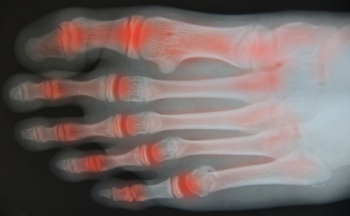

Rheumatoid arthritis (RA) is an autoimmune condition in which the immune system attacks healthy joints, causing pain and inflammation. These joints can be anywhere in the body, but some of the most commonly affected joints are those located in the feet and ankles. Symptoms that you may see if you have developed RA in the feet and ankles include pain, swelling, joint stiffness, difficulty walking, and joint deformities. You may also see rheumatoid nodules, dislocated toe joints, hammertoes, bunions, heel pain, Achilles tendon pain, and flat foot ankle pain. If you are experiencing the symptoms of RA in the feet and ankles, it is suggested that you see a podiatrist for treatment.

Arthritis is a joint disorder that involves the inflammation of different joints in your body, such as those in your feet. Arthritis is often caused by a degenerative joint disease and causes mild to severe pain in all affected areas. In addition to this, swelling and stiffness in the affected joints can also be a common symptom of arthritis.